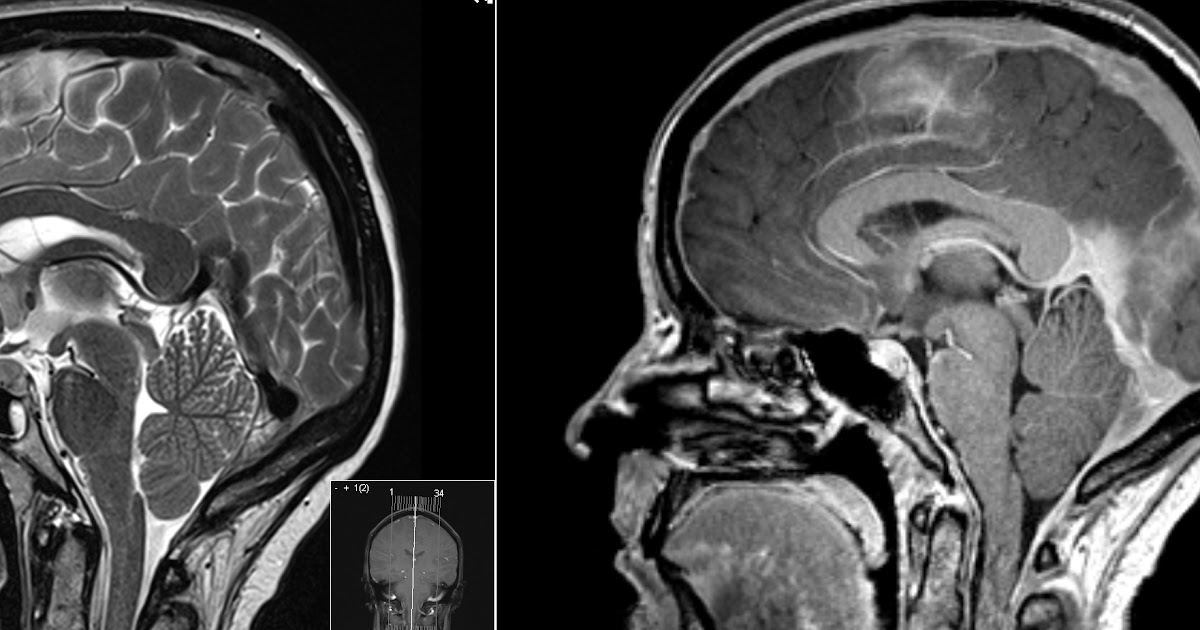

From radiologymri.blogspot.com

Radiology MRI CSF Leakage Intracranial Hypotension Csf Leak Differential Diagnosis Web spontaneous intracranial hypotension (sih) is a highly disabling syndrome secondary to spinal cerebrospinal fluid (csf) leak. Web cranial cerebrospinal fluid (csf) leaks occur when a dural tear or defect allows the passage of csf from the. Web diagnosing a csf leak. Web there are many ways to diagnose a csf leak including investigative techniques and medical imaging. Web cerebrospinal. Csf Leak Differential Diagnosis.